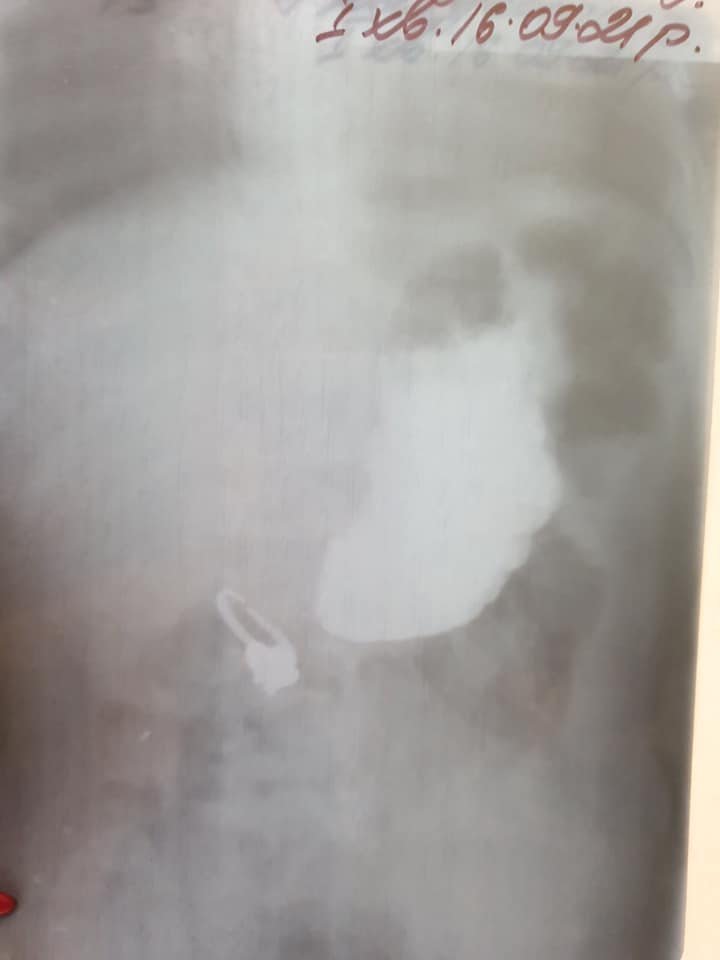

Во Львове врачи два часа спасали годовалую девочку. Ребенок проглотил кольцо.

«На рентгене хирурги увидели, что кольцо расторгнуто посередине (универсальный размер, чтобы регулировать) и имеет острые концы. Ситуация была сложной, потому что кольцо попало в двенадцатиперстную кишку, и часть кишки острым краем затянуло внутрь», — поделились врачи.

Кольцо доставали почти два часа. Медикам удалось его вытащить без операции. Девочка чувствует себя хорошо, и её уже отпустили домой.